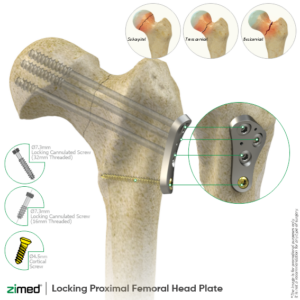

Large Fragment Locking Plate System

Locking Proximal Lateral Femoral Head Plates